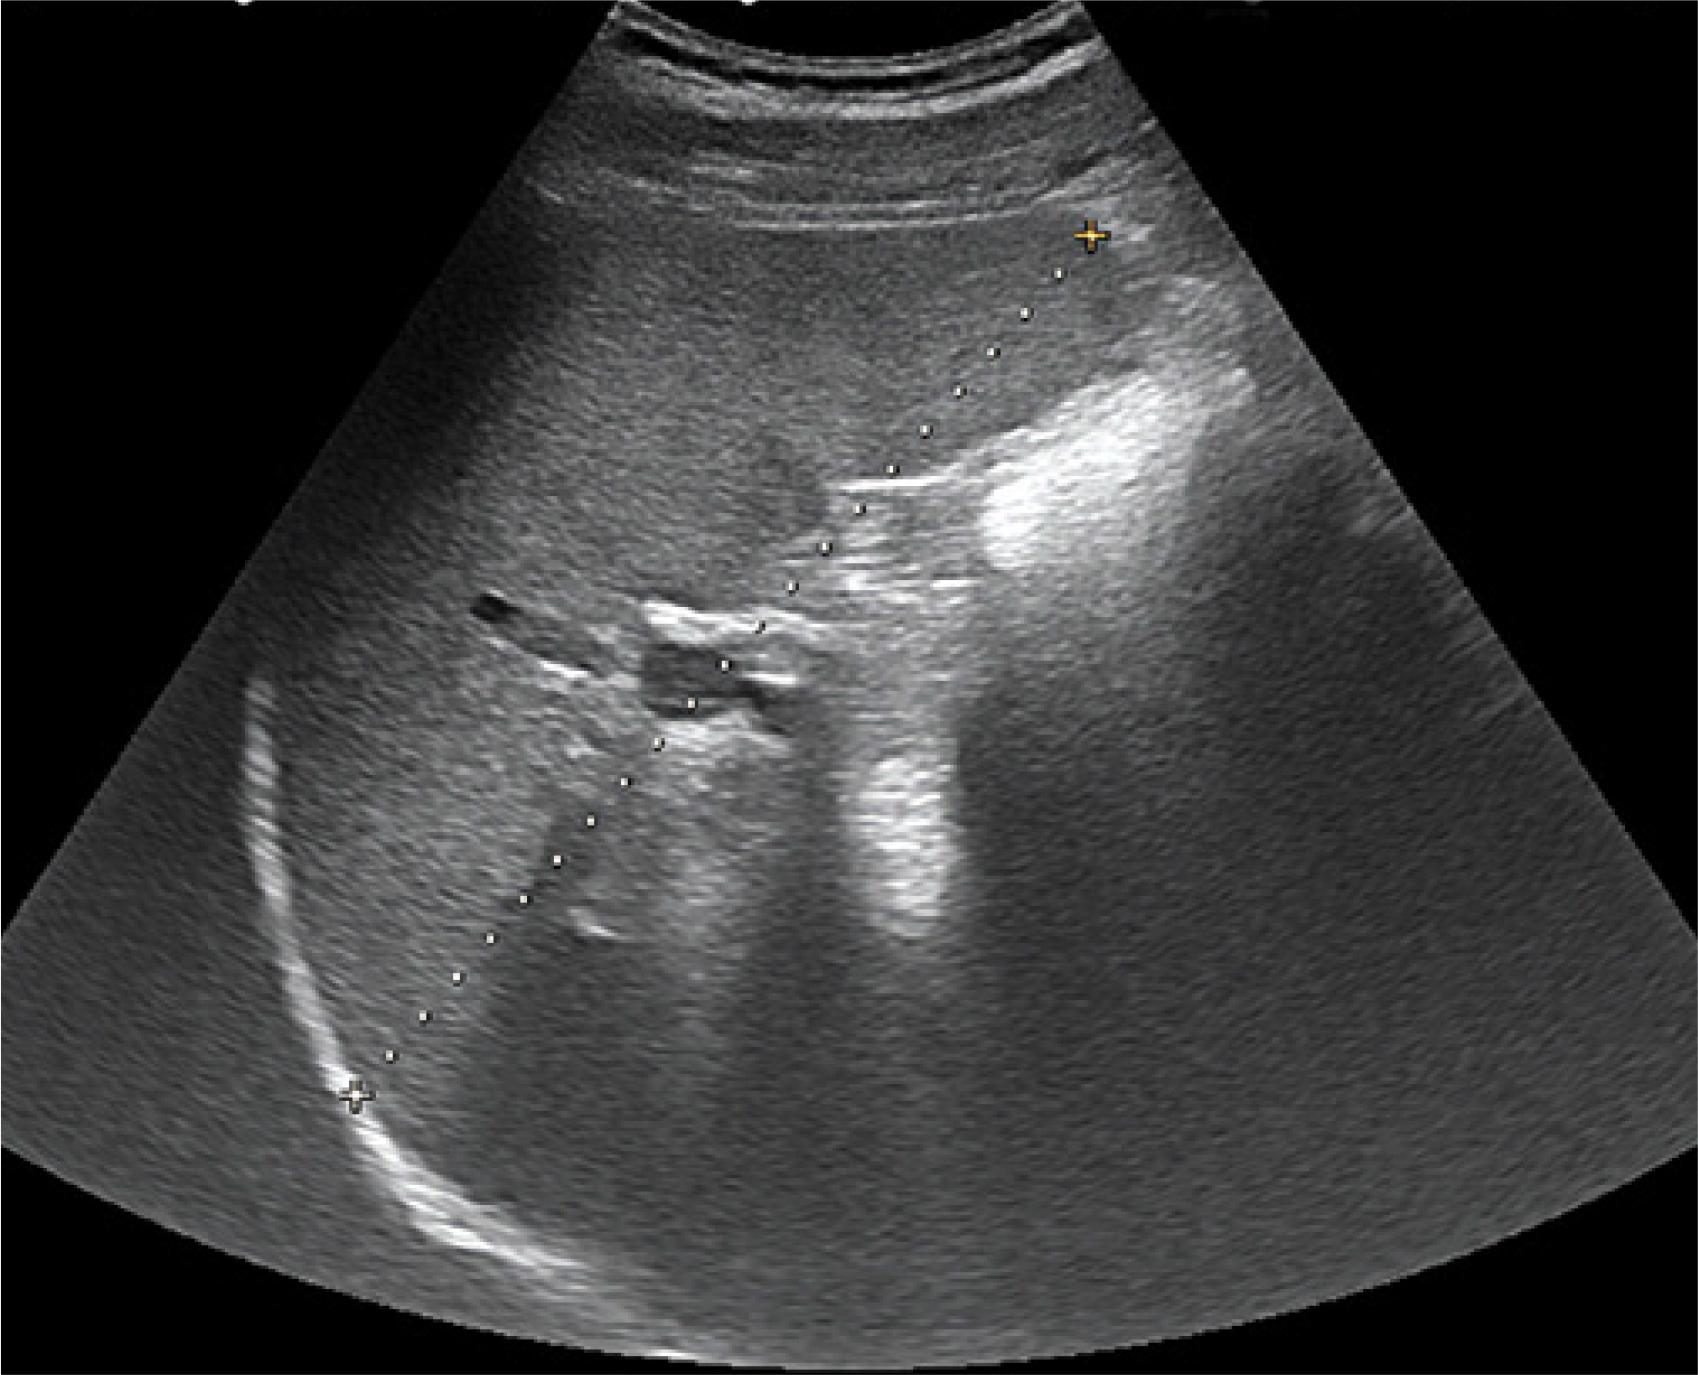

Fig. 1